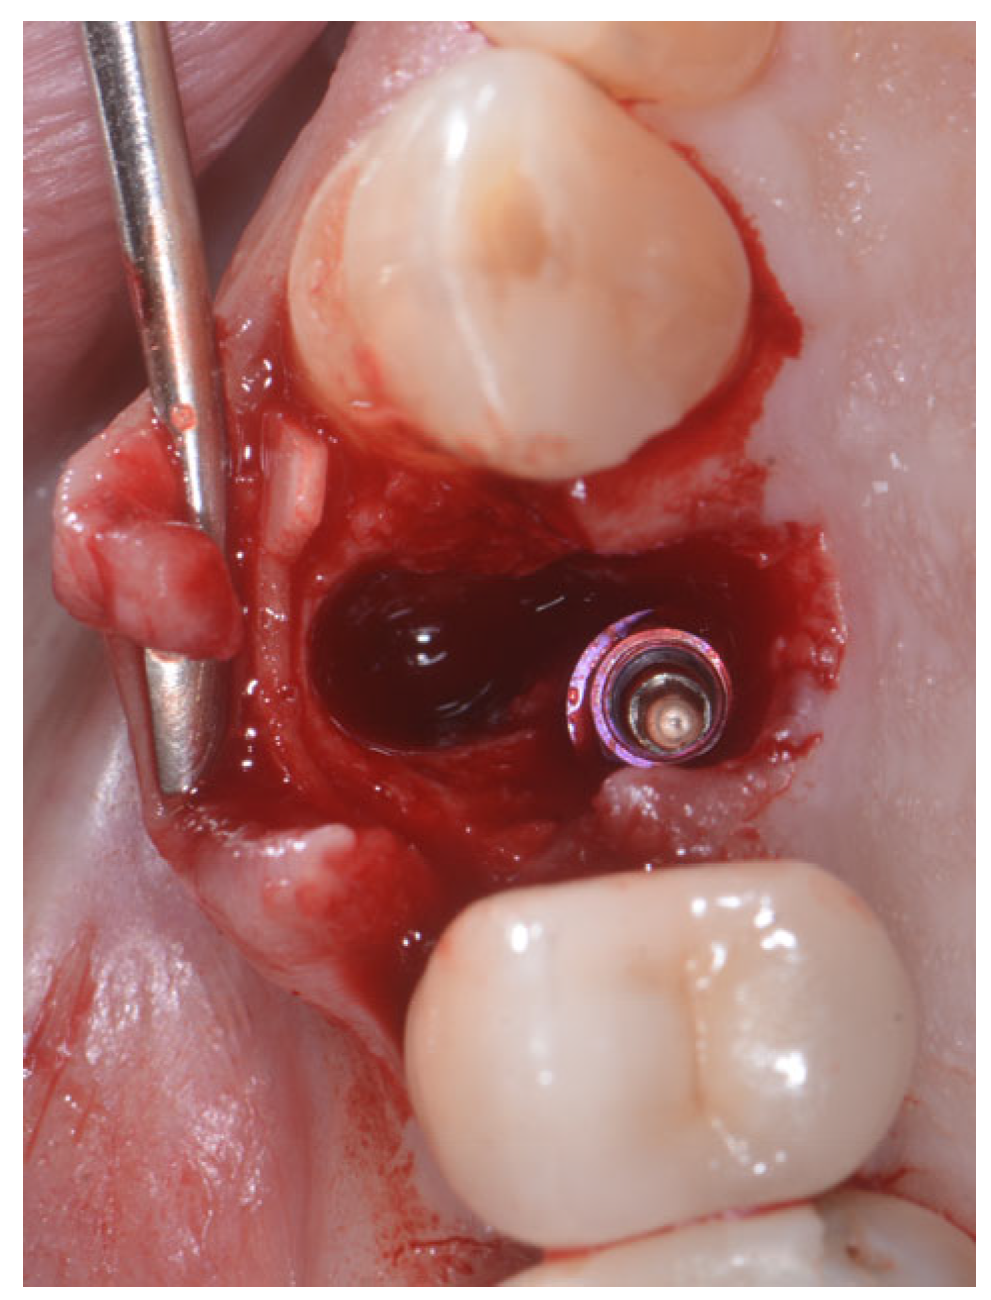

2.2. Surgical Technique

2.3. Indications

- Sockets that allow simultaneous implant placement;

- Sockets with intact buccal bone;

- Sockets with buccal fenestration.